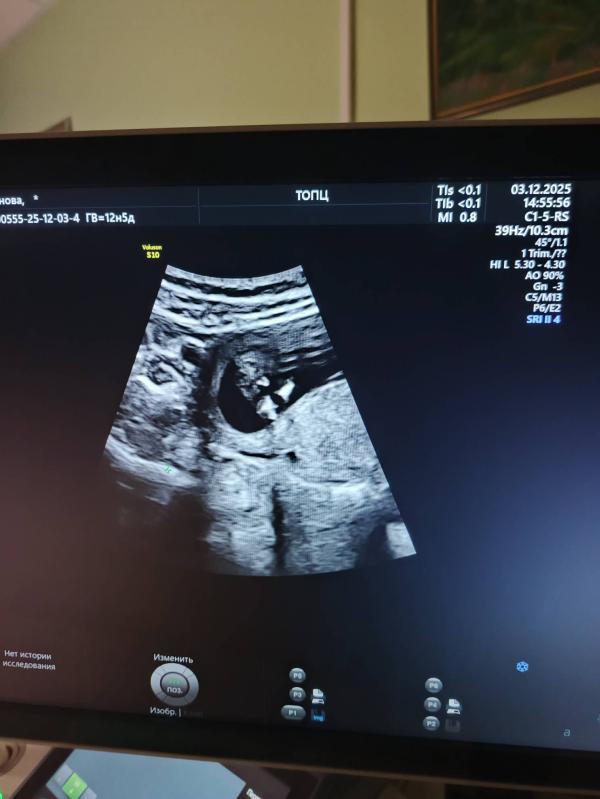

Первый скрининг: можно ли определить пол ребёнка на УЗИ?

Прошла первый скрининг 🤞 фух, тут есть кто различает пол? 🤣 не пацан ли, ммм? 🤣

На первом скрининге только половой бугорок есть и предположить пол можно исходя из угла полового бугорка

А на фото, мне кажется, это пуповину так видно или еще что, ручку там 😅

Предположили мальчика, сфоткать дали именно причинное место😄 сказали, что потом на втором посмотрим , насколько врач права😄